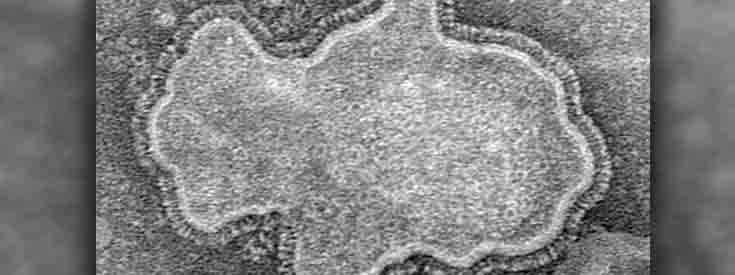

Infectious diseases have been major public health threats throughout history. Great strides have been made in the treatment and prevention of infectious diseases with antibiotics and vaccines however, new challenges continue to arise.

The URMC Infectious Diseases Division offers expertise in a wide range of areas including viral diseases such as Human Immunodeficiency Virus (HIV), Influenza, Respiratory Syncytial Virus (RSV) and Human Papilloma Virus (HPV) as well as bacterial infections including Methicillin Resistant Staphylococcus aureus, pneumococcus and Clostridium difficile and immunology. Our team has expertise in the care of transplant related infections, complex cardiac infections, infections in long term care facilities, sexually transmitted diseases and B cell immunology. Our division includes faculty at Highland, Rochester General and Unity Hospitals and maintains active clinical, research and educational missions.